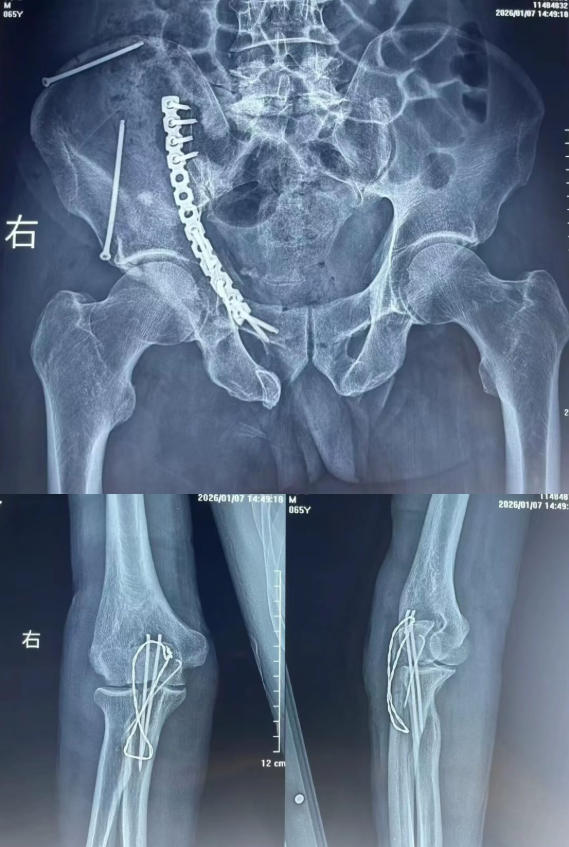

术后

待患者生命体征平稳,骨三科团队迎难而上,成功实施右骨盆多发骨折+尺骨鹰嘴粉碎性骨折切开复位内固定术。手术不仅将患者从死亡线上拉回,更充分考虑骨折愈合与远期功能恢复,为患者重新站立打下坚实基础。